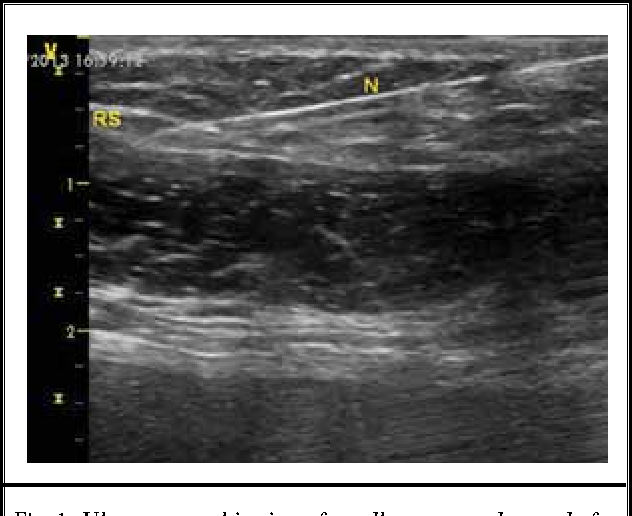

trigger img2

Trigger point visualised on Ultrasound

Early attempts to confirm the presence of myofascial trigger points using imaging, such as magnetic resonance elastography, showed promise but were not widely adopted. However, recent advancements in ultrasound have provided new hope.

Sikdar et al. have successfully utilized ultrasound to visualize and characterize trigger points. These trigger points appear as focal, hypoechoic (darker) regions with an elliptical shape, measuring approximately 0.16 cm. This breakthrough suggests that ultrasound could offer a more objective diagnosis of trigger points.

29. Trigger point visualised on Ultrasound. Image taken from https://www.bjanaesthesia.org.uk/article/S0007-0912%2817%2933096-9/fulltext